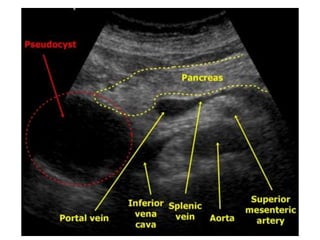

•Ultrasound TransAbd: 75 -90% sensitive

INVESTIGATIONS Labs: Persistently elevatedserum amylase Cyst fluid analysis(EUS+A): Carcinoembryonic antigen (CEA) and CEA-125 (low in pseudocysts and elevated in tumors); fluid viscosity (low in pseudocysts and elevated in tumors); amylase (usually high in pseudocysts and low in tumors)CEA (cystic neoplasm) Radiological Investigations •Plain X-ray: Not very useful •Ultrasound TransAbd: 75 -90% sensitive •EUS: helps plan therapy, not useful for Dx •CT : Most accurate (sensitivity 90-100%) •MRI –detection of solid component of cyst and in differentiating between organized necrosis and a pseudocyst